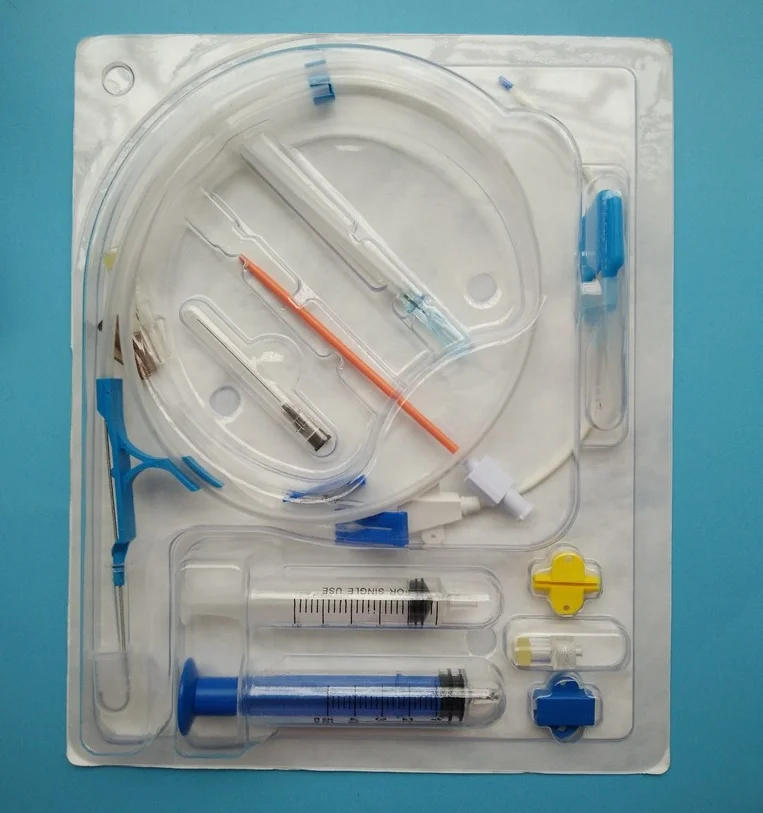

Вентрикуло-перитонеальный шунт: Показания и применение

Раздел: Фотоальбом решений